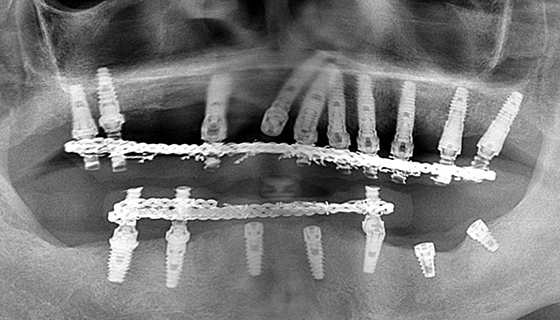

下顎にインプラント埋入→連結

下顎のインプラントも連結しました。

長期間経過観察

インプラントの自然脱落が相次いだので、長期間経過観察をし、最終的な人工歯を装着しました。

下顎にインプラント埋入→連結